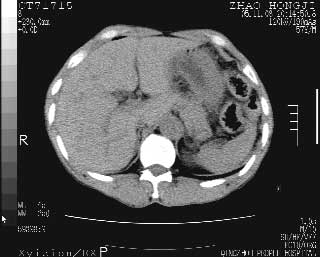

临床资料:男性,57岁,上腹部疼痛并5天,突然加重并延及全腹伴恶心5小时入院。胰淀粉酶化验在正常范围。检查:腹肌紧张,全腹压痛、反跳痛,尤以右上腹部为著。肠鸣音减低。血常规:wbc14.6x10/9, n:11.3x10/9 ,血压:135/90mmhg. 胸部透视:腹部肠腔轻度张气,未见其它异常改变。

肝右前缘少量积气,其他未见明显异常.考虑上消化道穿孔.

小网膜囊积气液,胃壁僵硬。考虑胃穿孔。

小膜网膜积液,肝缘气腹征,上消化道穿孔。

肝缘见少许气体,胰尾部见少许气体包饶(蓝色圈),12指肠上部或球部邻近胆囊周边也可见少许气体影(黄色圈),并忖托出胆囊壁,12指肠远段肠道内未见明显气体(白色箭)。

肝脏前缘见少量积气、胰尾部见少许气体包饶,肾前筋膜未见增厚,临床淀粉酶不高,意见:上消化道穿孔。

入院3小时后行剖腹探查术,见腹腔内大量脓性混浊液约1000ml,十二指肠球部溃疡穿孔,溃疡面约2.5x2cm,穿孔直径约0.6cm。胃内容物外益,周围组织炎性水肿明显。行十二指肠穿孔修补术。术后诊断:

1、十二指肠溃疡穿孔

2、弥漫性腹膜炎

对于少量的腹腔游离气体,ct检查较普通透视有绝对的优势,它不仅可以看到肝脏前上缘的气体,而且还能够看到小网膜区的游离气体。从而可以肯定诊断。各位分析战友的很好,感谢大家的参入!